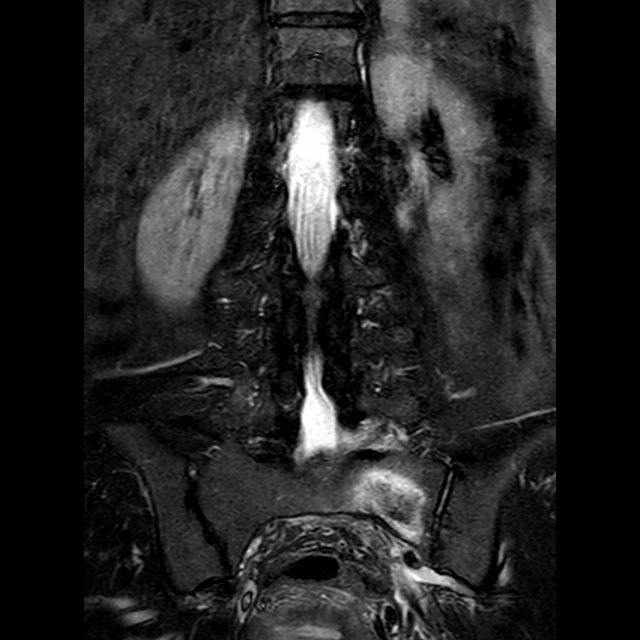

Undoubtedly, imaging – first of all, X-ray and MRI of the axial skeleton – plays an important role for the diagnostic assessment of patients with suspected axSpA and its differentiation from other conditions. A number of recent publications report a substantial variability in the interpretation of conventional radiographs and MRI, which is especially evident when local assessment is compared to a central expert’s judgment. Furthermore, an increasing number of publications cast doubt on the specificity of the "positive MRI" of sacroiliac joints, especially if MRI findings are interpreted without taking the clinical context into account.

The Assessment of Spondyloarthritis International Society (ASAS) has developed this interactive online case library, which compiles a number of carefully selected clinical cases representing the entire spectrum of axSpA and the most common differential diagnoses. For all cases presented, imaging is discussed in the context of clinical findings and laboratory test results.